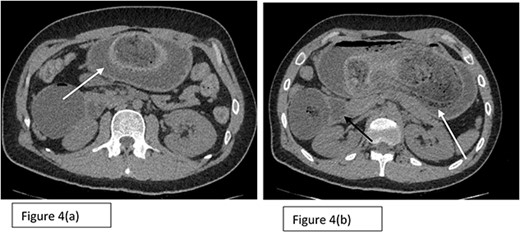

A computed tomography scan of the abdomen and pelvis showed a significantly distended stomach, duodenum, and proximal jejunum, with a large bezoar seen intraluminally (demonstrated in Fig. 4).

Axial sections (a) and (b) of CT scan showing the presence of Trichobezoar in the stomach (white arrows) with extension into the duodenum noted as well.